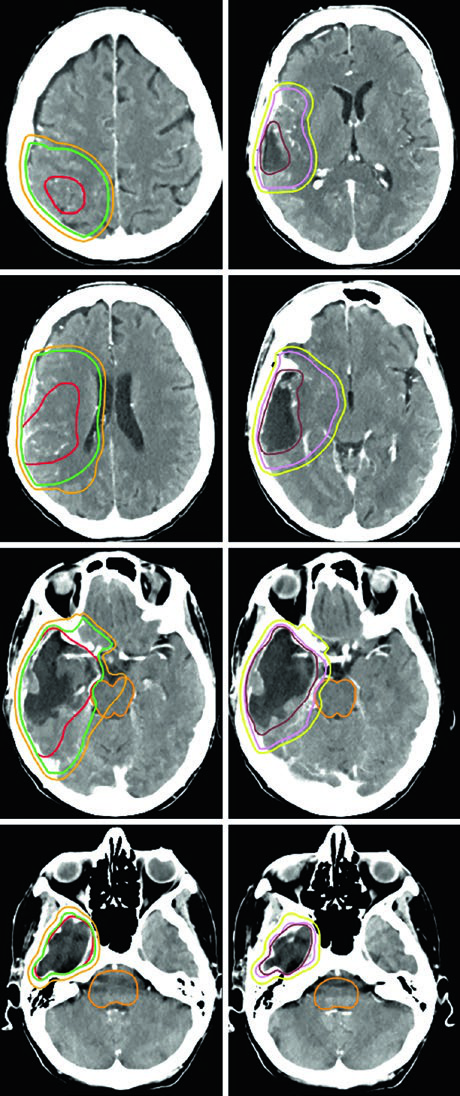

| Glioblastoma | Cone-down: PTV1 46 Gy (2 Gy/fx), PTV2 60 Gy (2 Gy/fx); or SIB: PTV1 50–51 Gy (1.67–1.7 Gy/fx), PTV2 60 Gy (2 Gy/fx) | GTV1: T2/FLAIR volume; GTV2: post-op cavity + residual on post-contrast T1 | CTV1: 2 cm constrained; CTV2: 2 cm constrained | 0.3–0.5 cm |

A critical practical point: anatomically constrained expansions mean the CTV does not cross midline, extend into the pre-pontine cistern, invade the skull, or pass through the tentorium into the posterior fossa. However, tracts at risk for contralateral tumor spread — such as the genu of the corpus callosum — must be explicitly included. This distinction is especially relevant in frontal glioblastomas approaching the callosal fibers.

The 40 Gy in 15 fractions schedule works well when minimal FLAIR signal extends beyond the enhancing tumor. In such cases, the GTV encompasses the resection cavity, residual tumor, and satellite nodules on post-contrast T1, with a CTV margin of just 1.0 cm — anatomically constrained at the tentorium.

For the most aggressive prognostic scenarios, ultra-hypofractionated delivery — 25 Gy in 5 fractions (or 30 Gy in 5 fractions as in the illustrated case) — uses 0.5 cm GTV-to-CTV margins. A posterior fossa glioblastoma exemplifies this approach, where the cochlea and brainstem are clearly visible as reference structures for dose optimization.